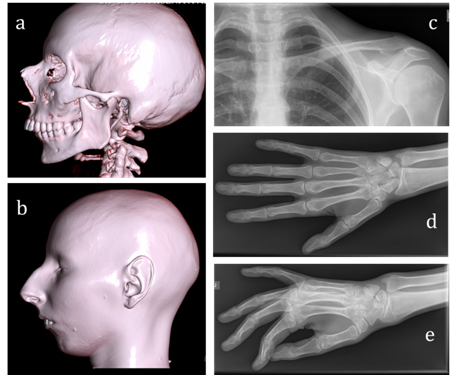

At examination of the patient a 6-minute walk test was 415m. The 12-lead electrocardiogram (ECG) showed sinus tachycardia (heart rate 104 BPM) with left axis deviation, left bundle branch block (QRS duration 124ms), normal corrected QT interval and nonspecific ST-T wave abnormalities. Holter monitoring of ECG showed an intermittent left bundle branch block (to 33%/24h); frequent premature ventricular contractions (PVCs) to19600/24h, coupled PVCs (158 couplets/24h), ventricular triplets (44/24h), non-sustained ventricular tachycardia (4 to 7 ventricular complexes with HR max up to 130BPM). ECG-strip demonstrating ventricular arrhythmia is presented in Figure 1A. The patient underwent echocardiography which demonstrated left ventricular dilatation with global systolic dysfunction, hypokinesis and moderate mitral valvular regurgitation. Diastolic and systolic diameters of the left ventricle were 57 and 47mm, respectively. The left ventricular (LV) ejection fraction (EF) was 33% and LV global longitudinal strain was -11,6%. Cardiac magnetic resonance imaging (MRI) confirmed criteria of DCM: LV dilatation (LV end-diastolic volume 177 ml, LV end-systolic volume 124ml) and global systolic dysfunction (LVEF 30%). Hypertrabecular structure of myocardial apex was found also.MRI findings of cardiomegaly are presented in Figure 1B, Figure 1C. Endomyocardial biopsies were examined, and no genetic markers of 8 cardiotropic viruses using PCR method were detected. Histological findings showed non-specific diffuse changes in myocytes (their size and nuclei varied) and interstitial fibrosis, no conclusive evidence of inflammation. Hormonal evaluation included follicle-stimulating hormone (140.2IU/L; menopausal range 25.8-134.8IU/L), luteinizing hormone (70.5IU/L; menopausal range 7.7-58.5IU/L), estradiol (201pmol/L; menopausal range 0.1-505pmol/L). Thyroid function test was consistent with subclinical hypothyroidism (thyroid stimulating hormone 6.98mIU/L; normal range 0.35-4.94mIU/L). Mini-Mental State Examination cognitive test was 20 scores (11-19 scores: medium dementia; 20-23 scores: mild dementia). Ultrasonography revealed a moderate thyroid hypoplasia. The patient refused to receive hormone replacement therapy. Pelvic ultrasonography revealed hypoplastic uterus, and the bilateral ovaries could not be clearly seen. However, the patient was capable to menstruate only with the support of estradiol and progesterone. X-rays examination of collarbones, extremity phalanges and cranium was performed to exclude mandibuloacral dysplasia taking into account signs of severe microretrognathia and adipose tissue thinning (lipodystrophy). Mandibuloacral dysplasia (MAD; OMIM 248370) is a rare, genetically and phenotypically heterogeneous, autosomal recessive disorder characterized by skeletal abnormalities including hypoplasia of the mandible and clavicles, acroosteolysis, cutaneous atrophy and lipodystrophy. X-rays revealed no evidence of MAD-specific bone dysplasia, i.e. distension of fontanel cranial sutures, dental abnormalities, clavicle hypoplasia and distal phalange acroosteolysis findings are presented in Figure 2.

Figure 2Findings of X-ray examination.

A, B) Cranium tomography (normal cranial suture, micrognatia) with 3-D scans reconstruction. There is no any evidence of MAD-specific bone dysplasia C) Normal clavicle (D&E) Absent of distal phalange acroosteolysis.